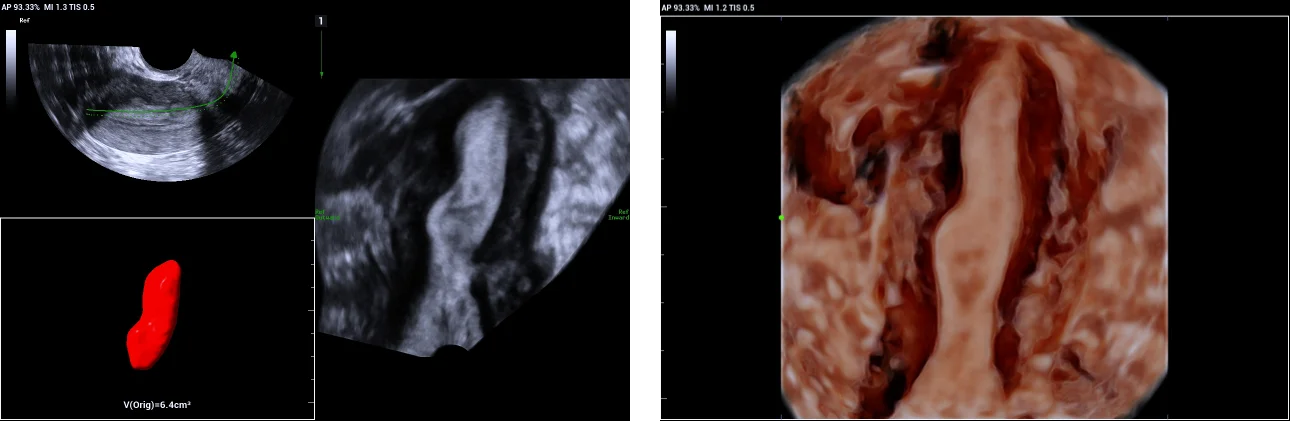

3. Uni-cornuate uterus.

Use of Smart ERA in diagnosis of Mullerian duct abnormalities - Uni-cornuate uterus

Unicornis-unicolis with no rudimentary horn, type b according to American Fertility Society classification.